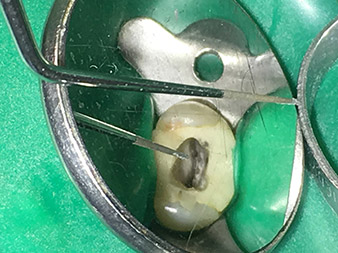

Spitze 4E

Schonendes Bearbeiten des Kavitätenbodens mit der Spitze 4E.

Die Spitze 4E - dieses Instrument eignet sich optimal zum Präparieren des Kavitätenbodens beim Übergang zu den Kanälen. Hier kann der Übergang Kanal - Kavitätenboden optimal abgerundet werden, sodass ein Trichter im Kanal entsteht.

Zusätzlich ist das Instrument die ideale Wahl, wenn es um das Freilegen der Kanäle von Dentinüberhängen geht. Insgesamt kann die Kavität mit dieser Spitze sehr effektiv und minimalinvasiv präpariert werden, indem Überhänge, Ecken und Kanten optimal abgerundet und geglättet werden.